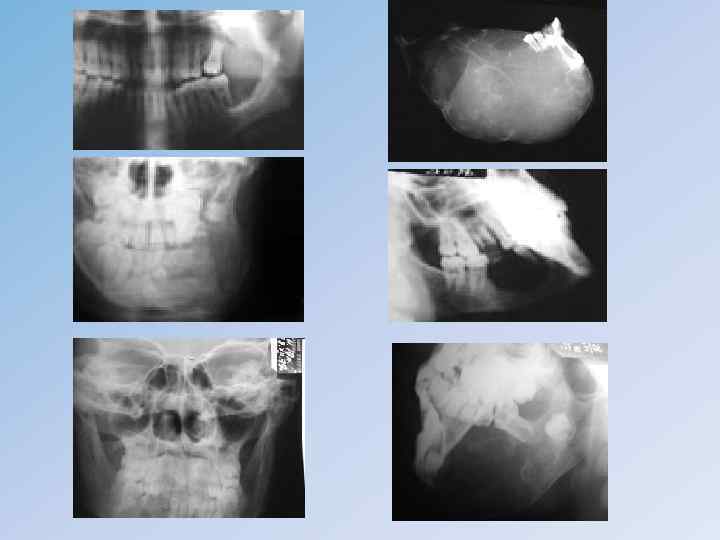

Множественно-очаговая миелома • • • поражает в основном плоские кости черепа, таза, позвоночника, грудину и реже – длинные трубчатые кости. Миеломной болезнью чаще болеют мужчины в среднем возрасте, но могут страдать дети и старики. Клиника. Заболевание начинается с болей в костях, затем отмечаются потеря веса тела и упадок сил, нередко возникает патологический перелом, который может быть и единственным клиническим признаком болезни. Злокачественный процесс быстро прогрессирует, осложняется поражением почек, сопровождаемым выделением патологического белка Бенс-Джонса и метастазами в селезенку, печень, лимфатические узлы. Развиваются кахексия, анемия, гиперпротеинемия, гиперкальциемия, ускоряется СОЭ. Рентгенологическая картина множественной миеломы характеризуется первоначально диффузным остеопорозом, затем появляются множественные овальные очаги остеолиза, прежде всего в плоских и коротких костях, содержащих красный костный мозг: грудине, ребрах, позвонках, своде черепа, тазовых и трубчатых костях. Пораженная кость представляется расширенной с истонченным корковым слоем, без периостальной реакции, как бы продырявленной во многих местах пробойником.

Солитарнаямиелома • (плазмоцитома) наблюдается преимущественно в плоских костях. В пораженной кости образуется очаг декальцификации, медленно увеличивающийся. Иногда участок остеолиза может достигать больших размеров, напоминать кистовидное образование без реактивного периостита. • Клиническая симптоматология выражена не так ярко, как при множественной миеломе, однако патологические переломы наблюдаются часто. • Диагностика миеломной болезни часто затруднена из-за сходной клинической и рентгенологической картины со многими заболеваниями костной системы. • К ним относятся: гигантоклеточная опухоль, остеолитическая остеосаркома, солитарные метастазы рака, болезнь Педжета и Реклинхаузена и др.